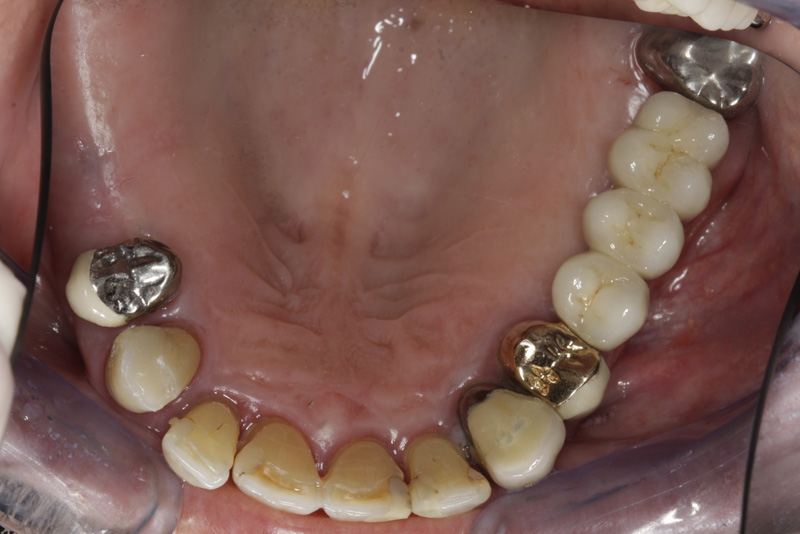

V případě chybění většího počtu zubů v postranních úsecích čelistí je možné ošetření pomocí implantátů, které nahradí ošetření pomocí snímacích náhrad kotvených na zbývajících zubech nebo patře.

Podmínkou je opět dostatečné množství kosti.

Protetické řešení může být pomocí můstku, který je kotvený na implantátech nebo pomocí jednotlivých korunek na implantátech.

V zásadě je možné do těchto můstků zařadit i přirozené zuby, zejména pokud je potřeba tyto zuby ošetřit proteticky

- korunkami. Korunky nebo můstky mohou být na implantáty nacementovány nebo přišroubovány.

Zdravé zuby zůstanou zachovány a přitom náhrady jsou pevné, jako na vlastních zubech